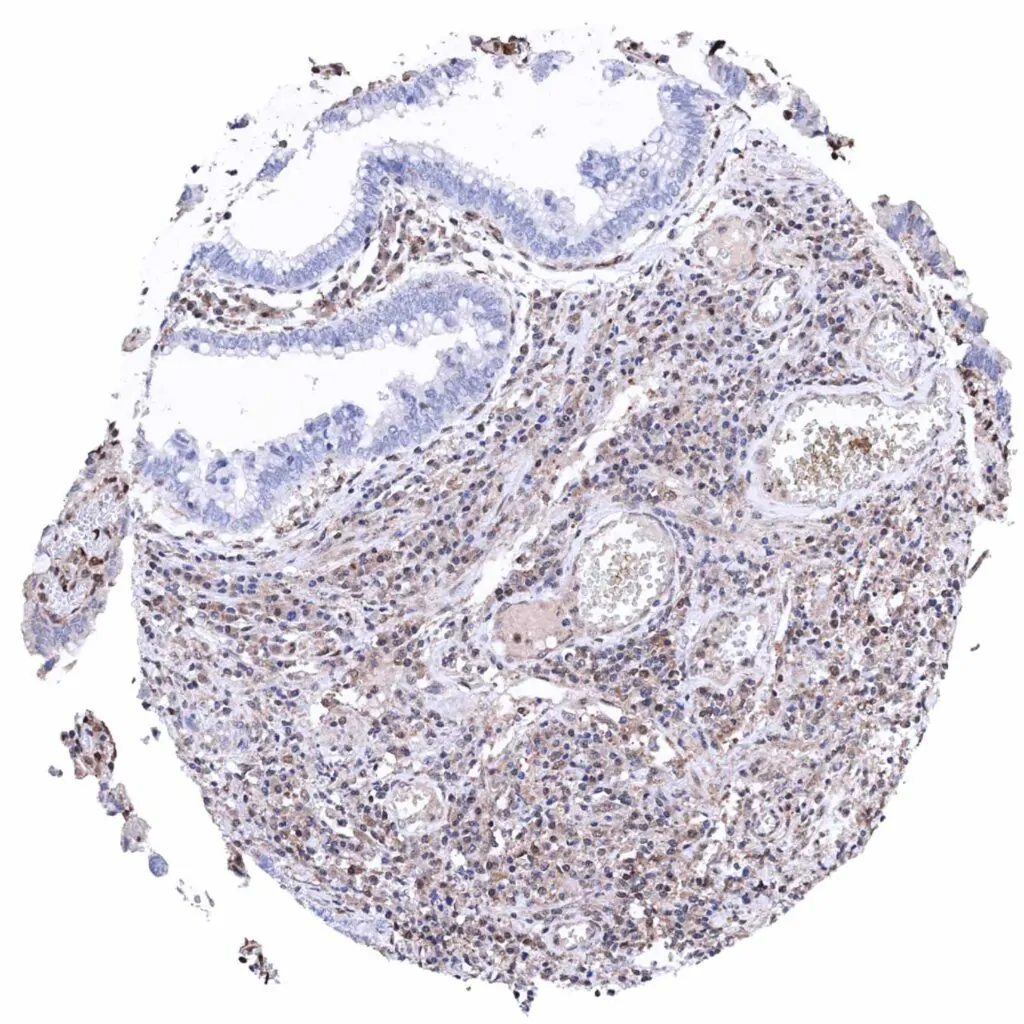

Ovary – Serous high-grade carcinoma with complete absence of MTAP staining in tumor cells. Significant MTAP staining of inflammatory and stromal cells